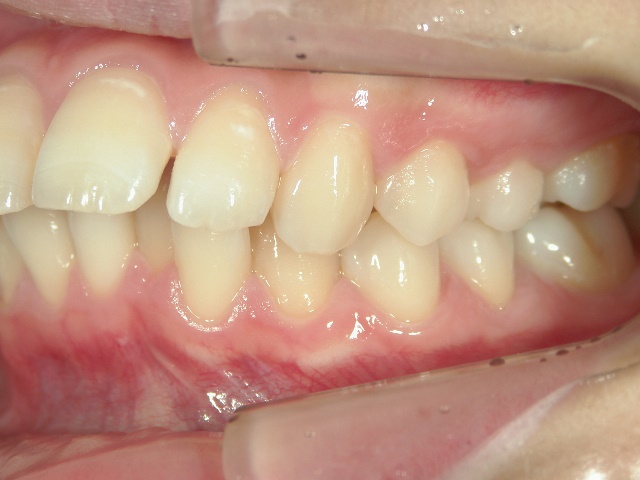

矯正歯科 治療前